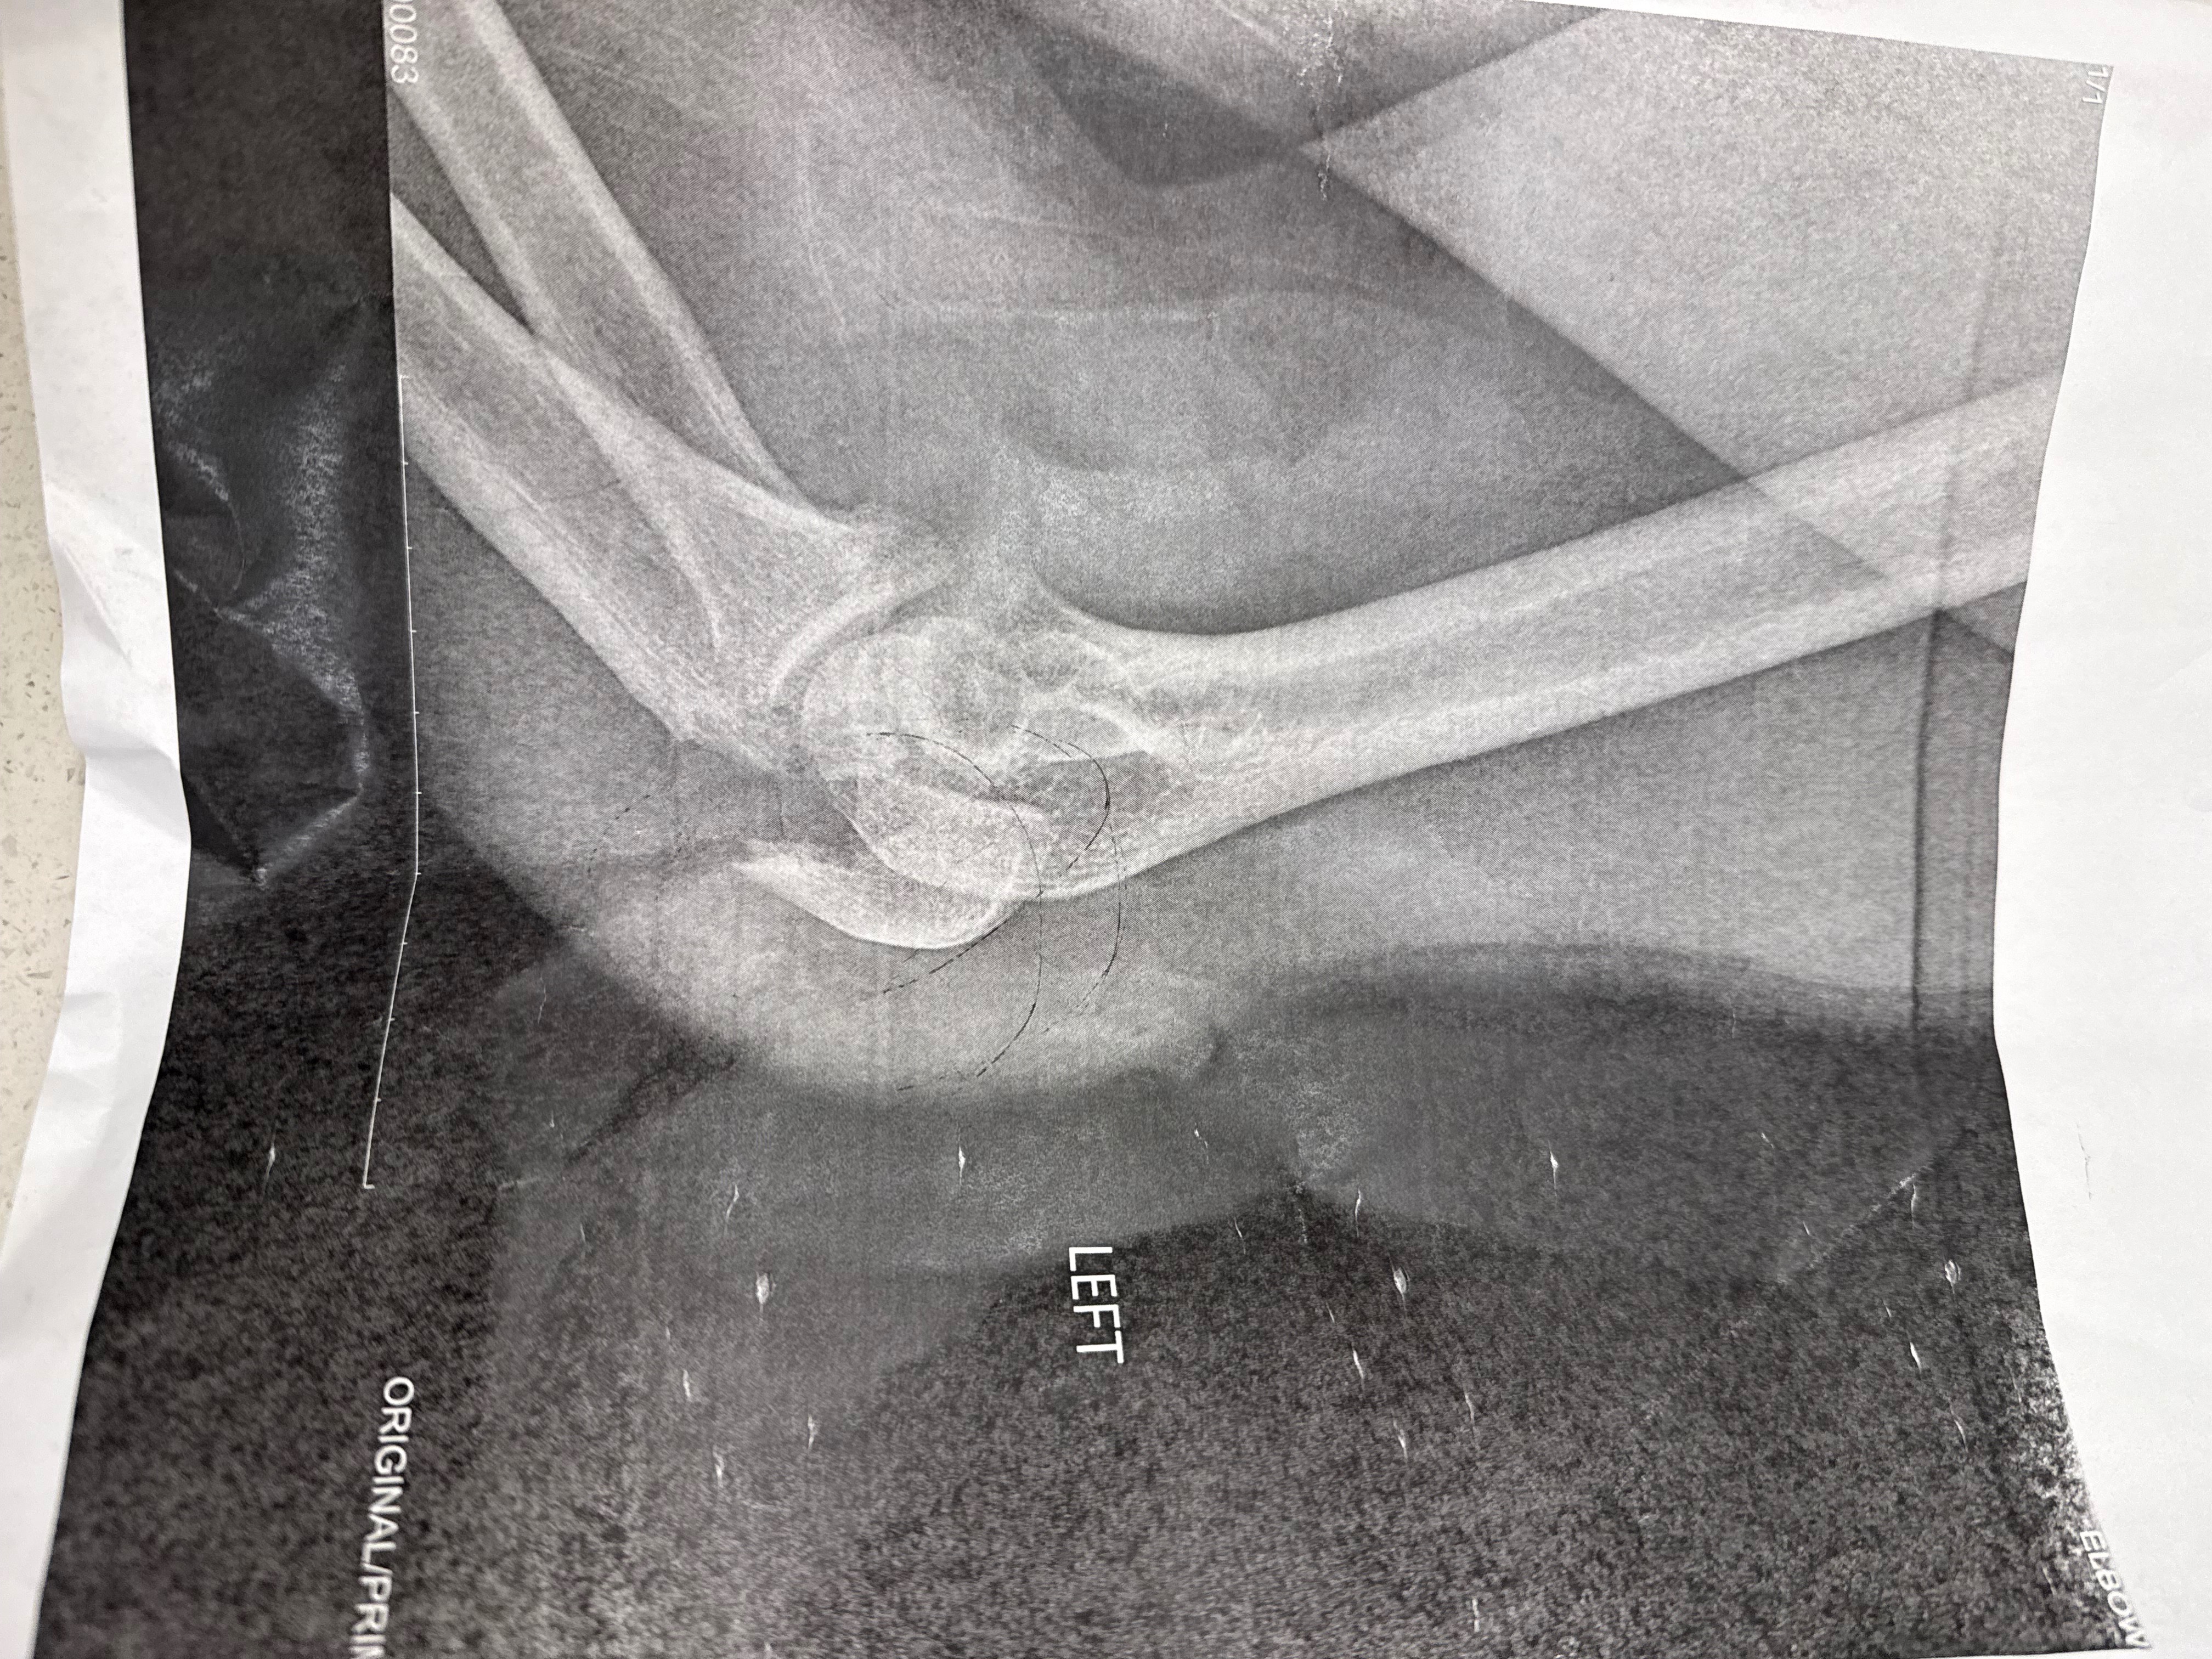

Hi my name is Matthew Blisard, I’m a Charlotte native and moved back here in 2016 to be with my family. I bartend at a local favorite Irish bar, Tyber Creek. I love bartending and enjoy roaming my neighborhood south end on my days off. A few weeks ago unfortunately, I had a bad fall on one if those darn scooters they have around town and broke my elbow. The injury was serious enough that I needed surgery, and now I have two plates in my arm. I was shocked to find out that my insurance won’t cover the bill of over $70,000 for the procedure. On top of that, I work as a bartender, so being out of work for several weeks means I have no income coming in right now.